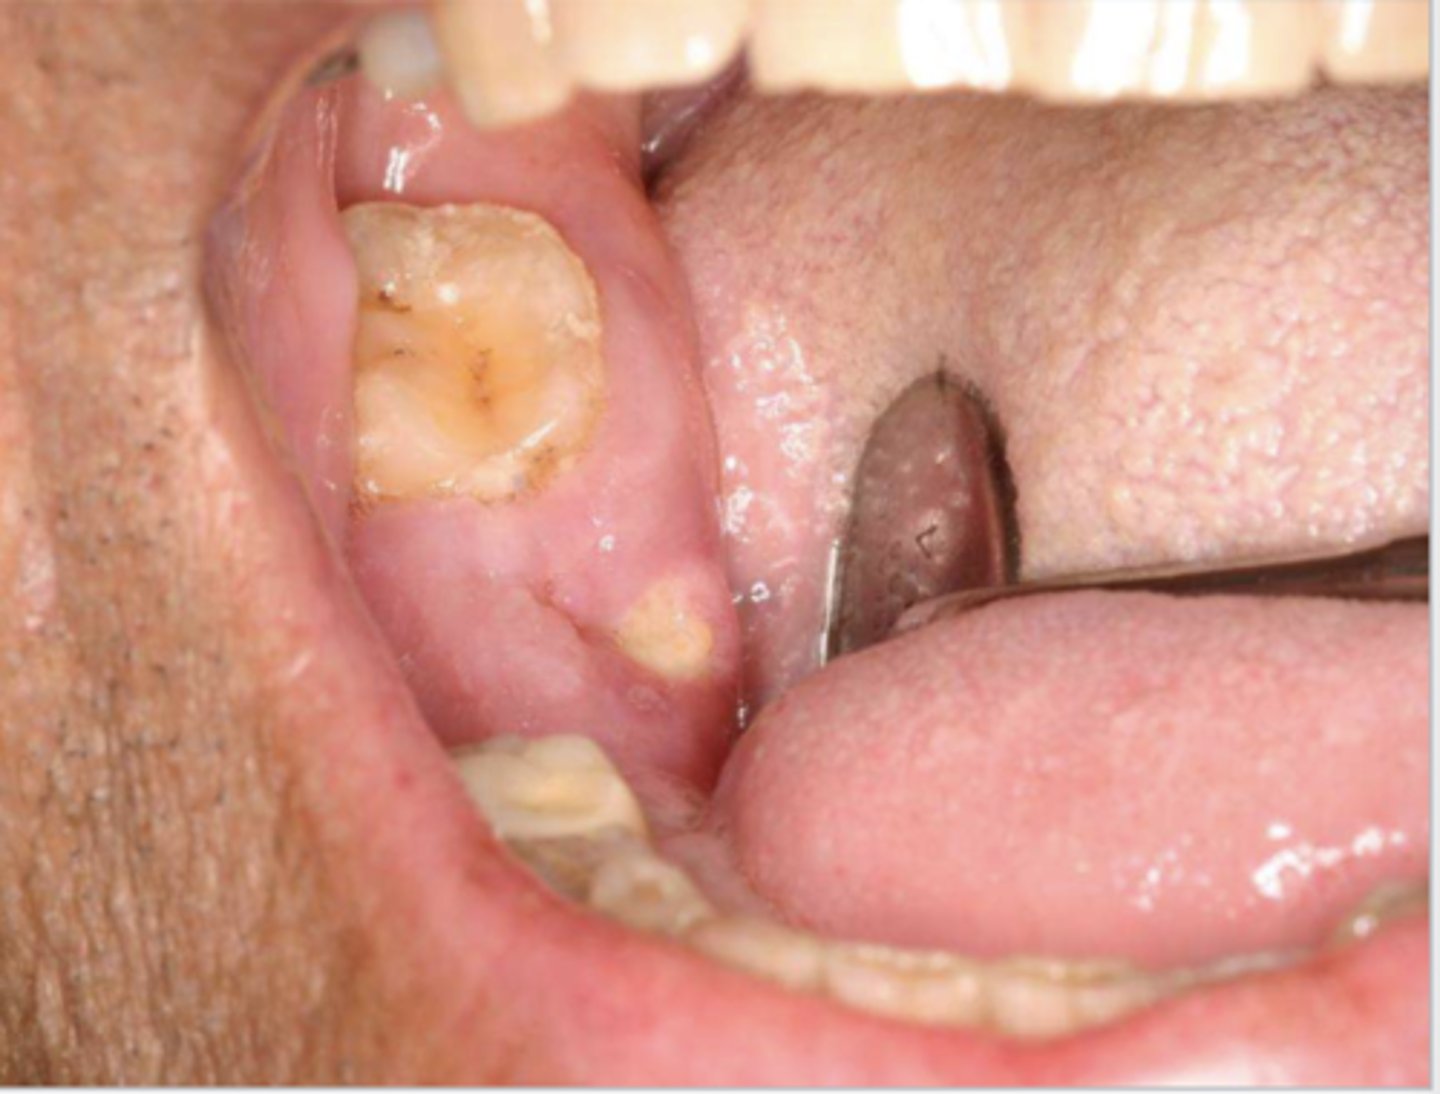

Find the lesion. What diagnosis differential would you consider?

well-demarcated papillary lesion on the buccal dental papillae between #20 & #21; Possible Differential:

-HPV --> papillary, will need to confirm with biopsy, HPV testing

-squamous cell carcinoma

-verruciform xanthoma --> benign lesion that may resemble squamous papillomas or squamous cell carcinoma

*v. xanthoma is what this lesion is but there's no way to differentiate from the differential clinically w/o HPV testing/biopsy